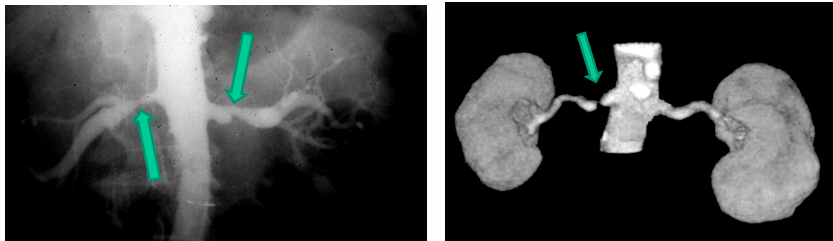

-”string of beads” characteristic of medial fibromuscular dysplasia

-renal artery stenosis

renovascular hypertension

-diagnosis: renin levels can be high but normal levels do not rule out renal artery stenosis

-imaging studies: sonography with duplex doppler, magnetic resonance angiography, CT angiography, angiography

-due to fibromuscular dysplasia in young individuals- treat with angioplasty

-due to atherosclerotic disease in older individuals with CV risk factors: suspect with pre-existing peripheral vascular disease or long history of smoking, recurrent flash pulmonary edema, treatment with angioplasty + stent placement